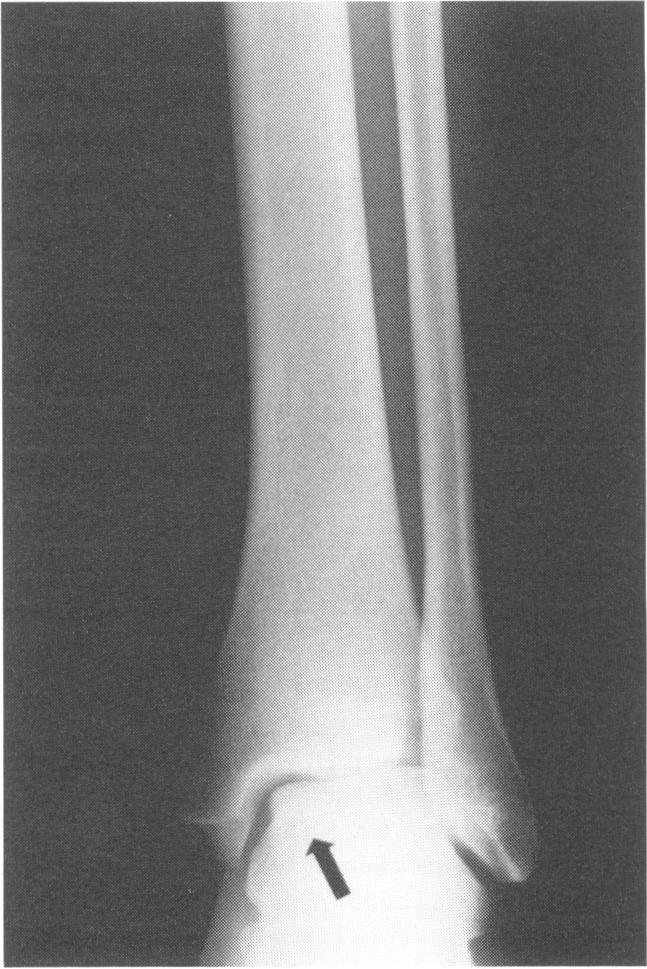

Maisonneuve fracture dislocation of the ankle.

Ligamentous injuries of the ankle are usually benign and may be managed satisfactorily by nonoperative measures. This is not true, however, of the Maisonneuve variant. In this paper we present a case report of a high school athlete who sustained a Maisonneuve fracture dislocation of the ankle. The diagnosis was missed initially, because of an incomplete examination. The subsequent physical and radiographic examination revealed the proper diagnosis. Guidelines for the evaluation and appropriate treatment are discussed.